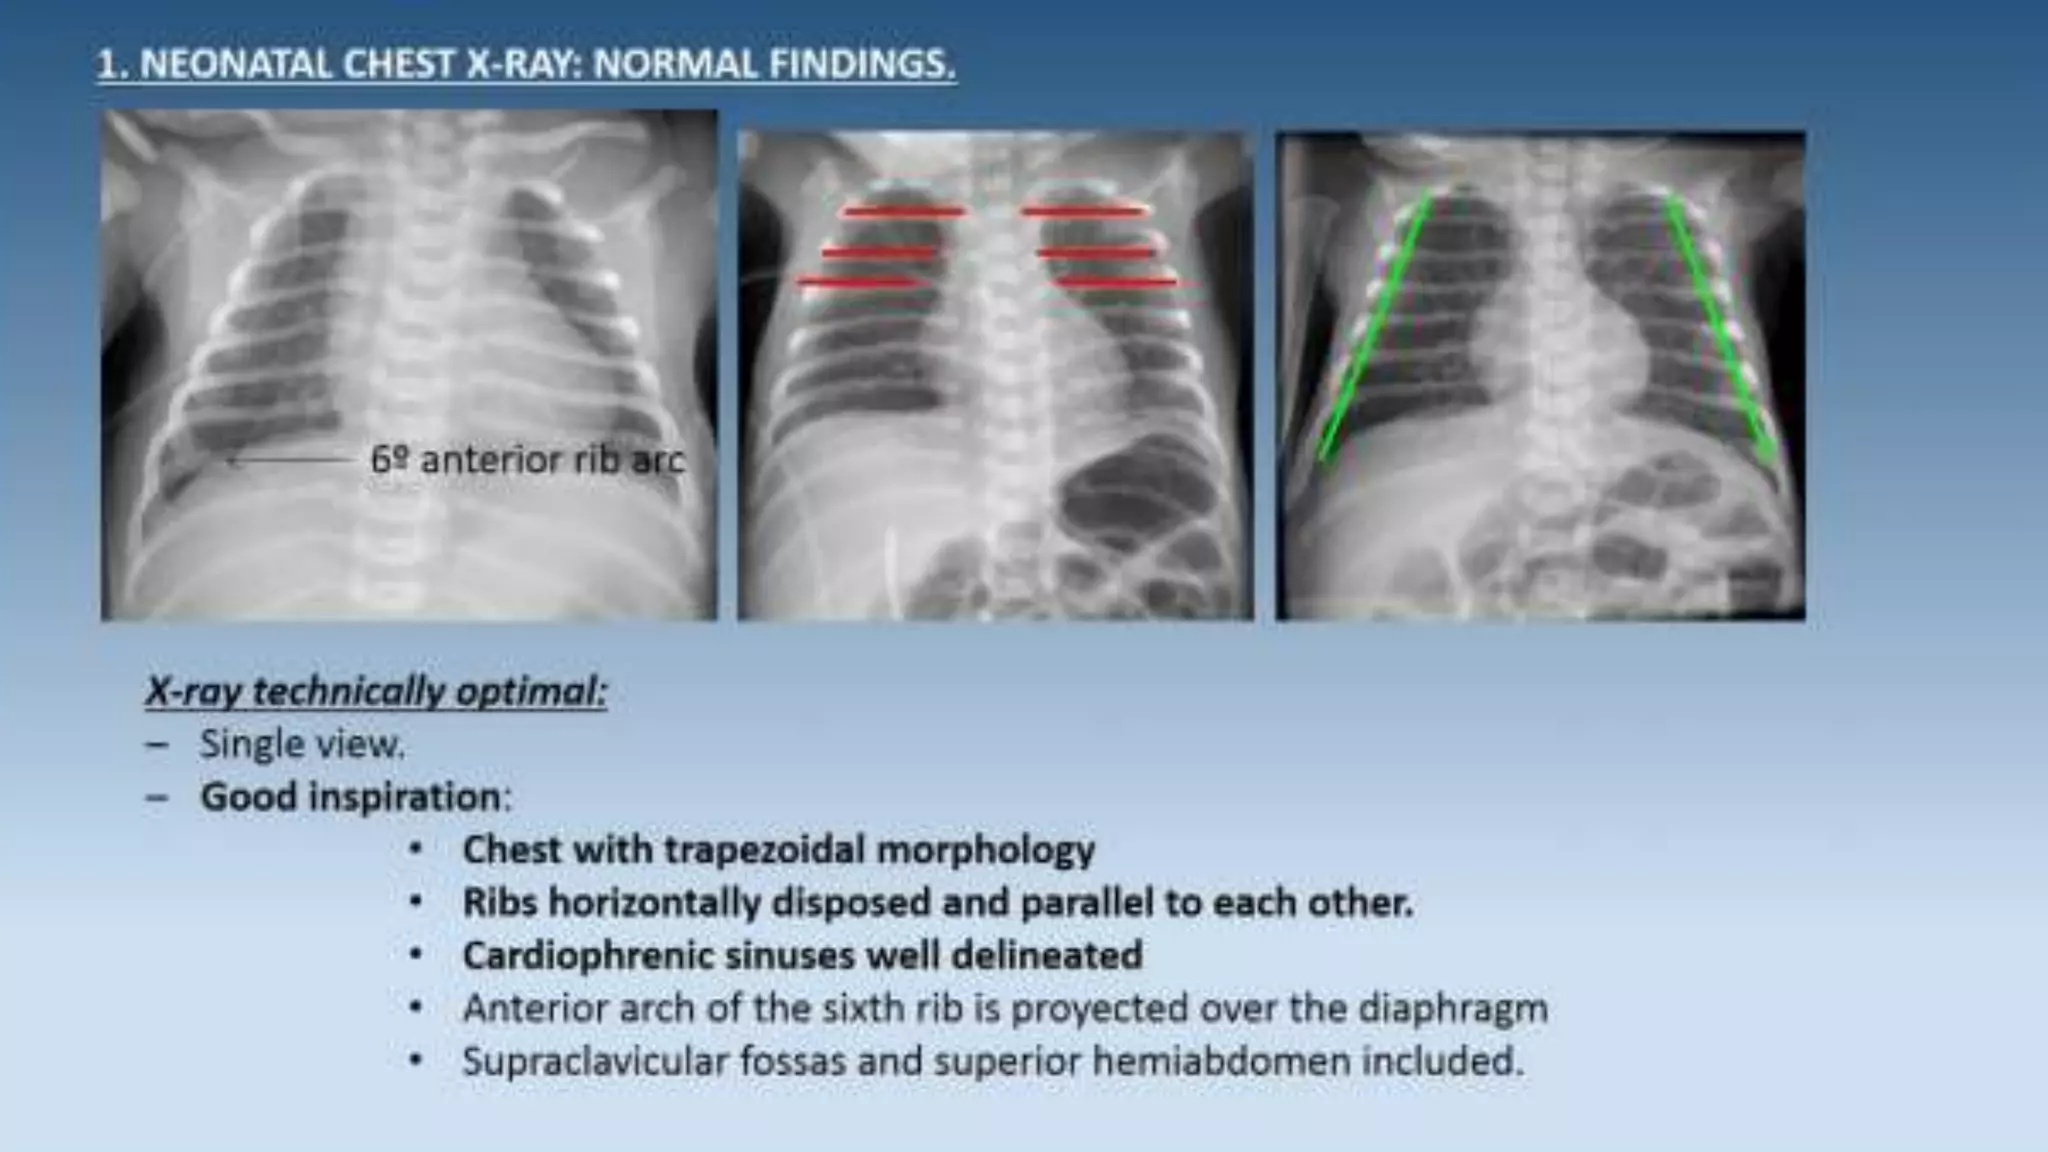

This document provides an overview of neonatal chest x-rays, including when they should and should not be performed, what a normal x-ray looks like, common positions of tubes and catheters, and common causes of respiratory distress in neonates. It discusses the appearance of a normal chest x-ray as well as conditions like respiratory distress syndrome, transient tachypnea of the newborn, meconium aspiration syndrome, and pneumonia. Surgical conditions like diaphragmatic hernia and esophageal atresia are also reviewed.